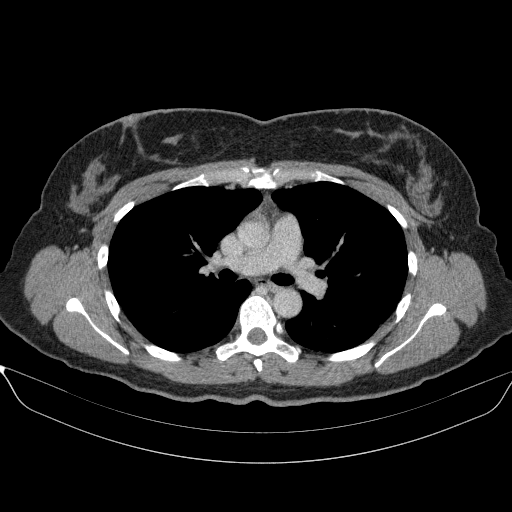

Original VENOUS CT scan

Full window (WL 1023.5, WW 4095 β†’ Low βˆ’1024, High +3071)

Actual HU range: [-1024.0, 1298.0]

Lung window (WL -600, WW 1500 β†’ Low βˆ’1350, High +150)

Actual HU range: [-1024.0, 150.0]

Mediastinum window (WL 40, WW 400 β†’ Low βˆ’160, High +240)

Actual HU range: [-160.0, 240.0]